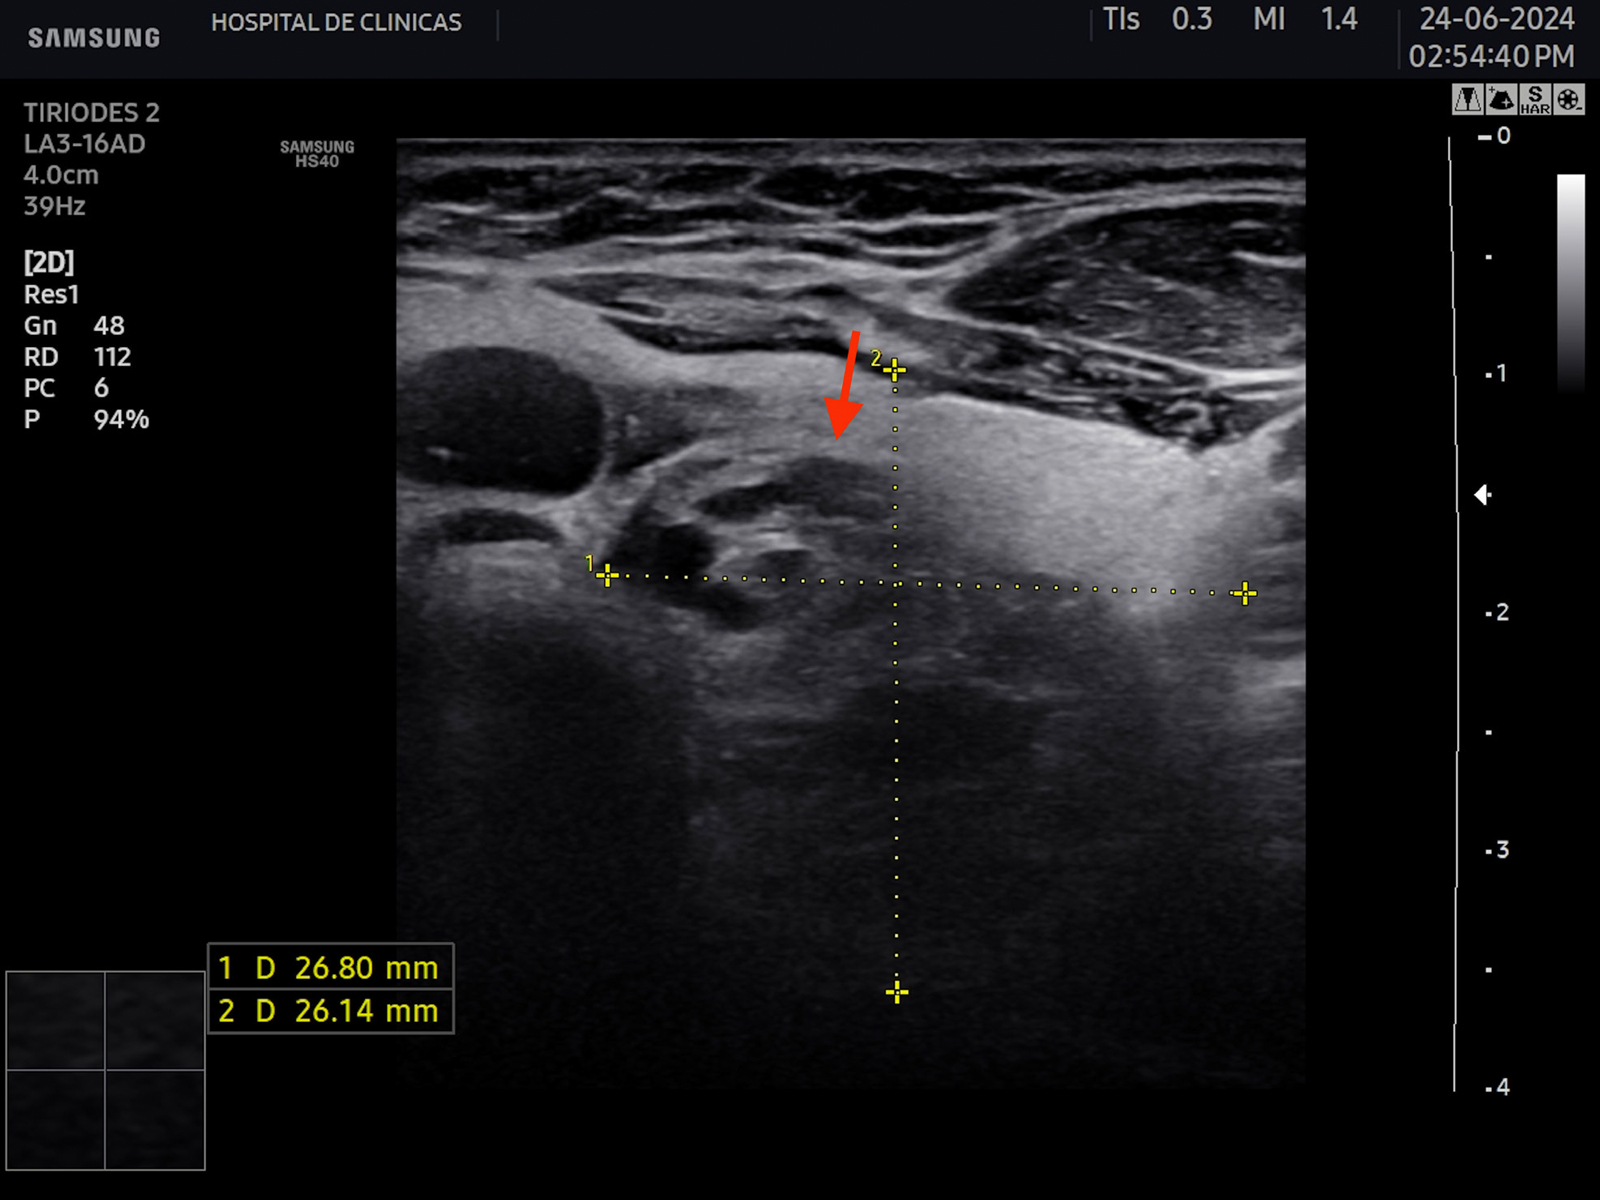

La hipoecogenicidad del parénquima glandular se correlaciona con el grado de infiltración linfocitaria, atrofia de los folículos y disminución del contenido coloide. Esto genera menos reflexión de las ondas sonoras y, por lo tanto, menor ecogenicidad6. Se puede encontrar además aspecto micro o macronodular. Se denominan seudonódulos a las áreas de intensa infiltración linfocitaria local, las cuales deben ser diferenciadas de los nódulos verdaderos que requieren otro seguimiento6. En la figura 6 se aprecian estas características comentadas.

Figura 6: Corte transversal y longitudinal de tiroides de paciente con tiroiditis de Hashimoto. Se señala la disminución de la ecogenicidad, estructura

heterogénea, seudonodular.